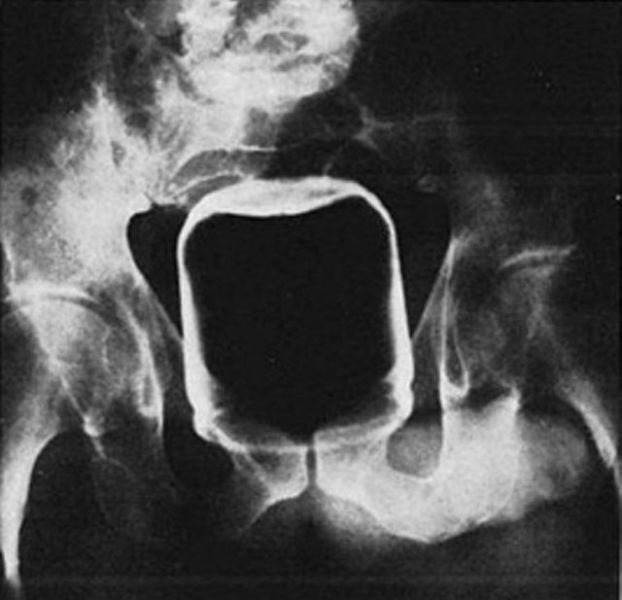

Vibrator and tongs

Vibrator in the rectum. The patient attempted self-removal with a pair of salad tongs, which also became lodged.